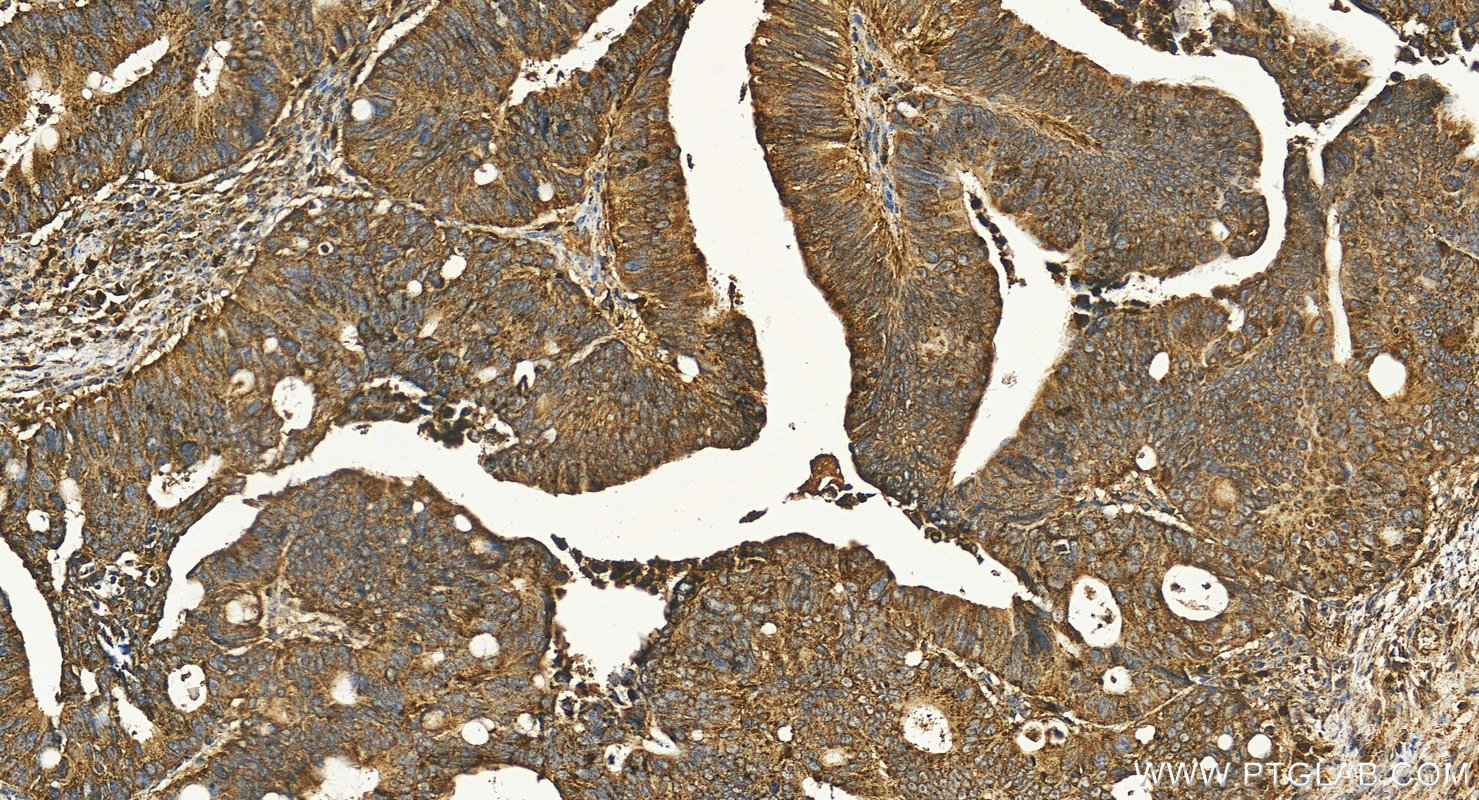

| Positive IHC detected in | human colon cancer tissue, human gliomas tissue, human liver cancer tissue, human pancreas tissue, human placenta tissue Note: suggested antigen retrieval with TE buffer pH 9.0; (*) Alternatively, antigen retrieval may be performed with citrate buffer pH 6.0 |

LAMP1 (also known as CD107a) is a 90-120 kDa heavily glycosylated membrane protein enriched in the lysosomal membrane. LAMP1 functions to provide selectins with carbohydrate ligands. This protein has also been shown to be a marker of degranulation on lymphocytes such as CD8+ and NK cells and may also play a role in tumor cell differentiation and metastasis.